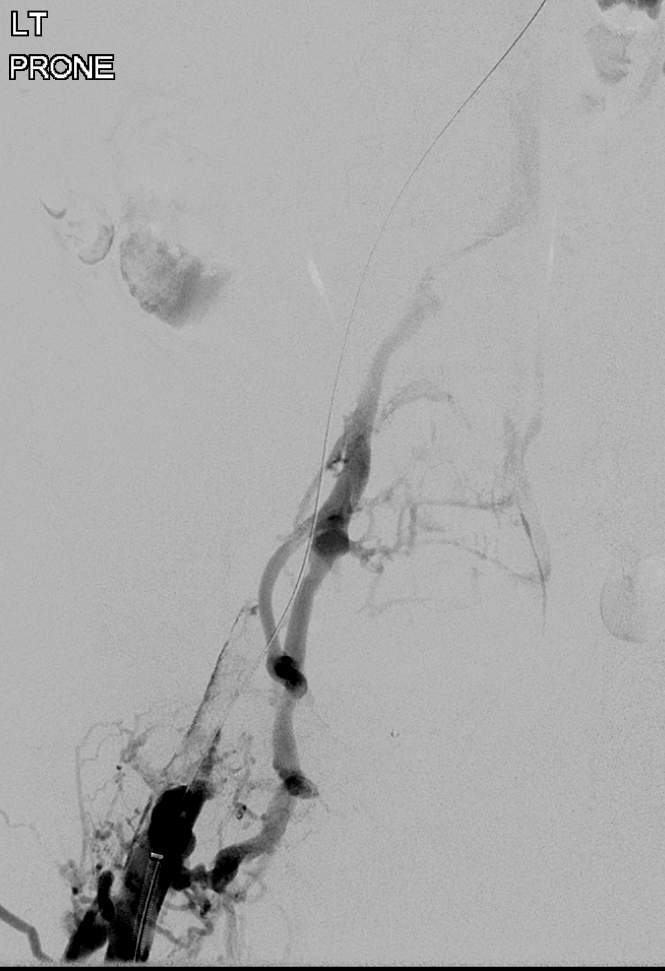

Double the vessel, double the clot! Prone, Popliteal access, #ClotTriever. Wired up each side sequentially, and pulled out those dark, sticky clots. #DVT #IRad

Rex Ray tweet media